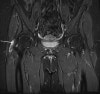

(T1 : Hypointense to intermediate, T2 : Hyperintensity with bursal distension, Heterogenous hemorrahage or proteinaceous debris, T1 C+ : Peripheral enhancement)

MRI : 전자 점액낭염(Trochanteric bursitis)